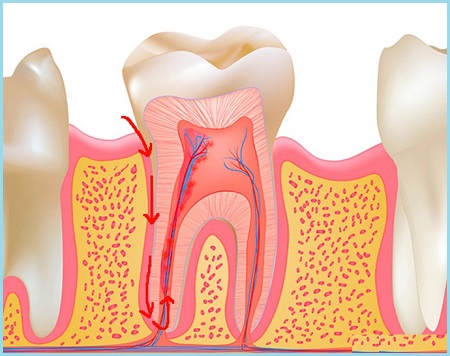

Ткань, окружающая корни зуба и удерживающая его в альвеоле, получила медицинский термин — периодонт. Соответственно, ее воспаление классифицируют как периодонтит. Локализация очага воспаления обуславливает разделение периодонтита на апикальный и маргинальный.

Причина возникновения

Причиной развития заболевания в большинстве случаев становится глубокий кариес и пульпит. При пульпите воспаление поражает мягкие ткани зуба – пульпу, затем распространяется на периодонт. Этот процесс способствует формированию кисты – своеобразного мешочка, заполненного жидкостью. В данном случае речь идет о серозном периодонтите.

Лечение

Принципы лечения всех форм периодонтита сводятся к устранению воспаления в области верхушки корня зуба. Достигается это разными способами. Сложность лечения определяется степенью развития процесса, его распространенностью, анатомией зуба и корней, возрастом пациента.